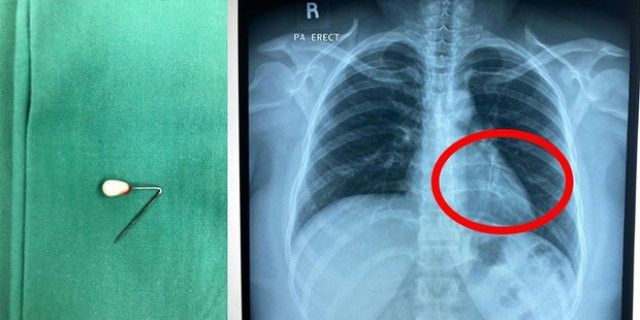

Tuwiran menjelaskan dari hasil foto rognsen, terlihat jarum pentul tersebut masuk ke sebelah dada kiri pasien. Bahkan dari kabar rumah sakit, jarum tersebut hampir saja masuk ke paru-paru Dinda.